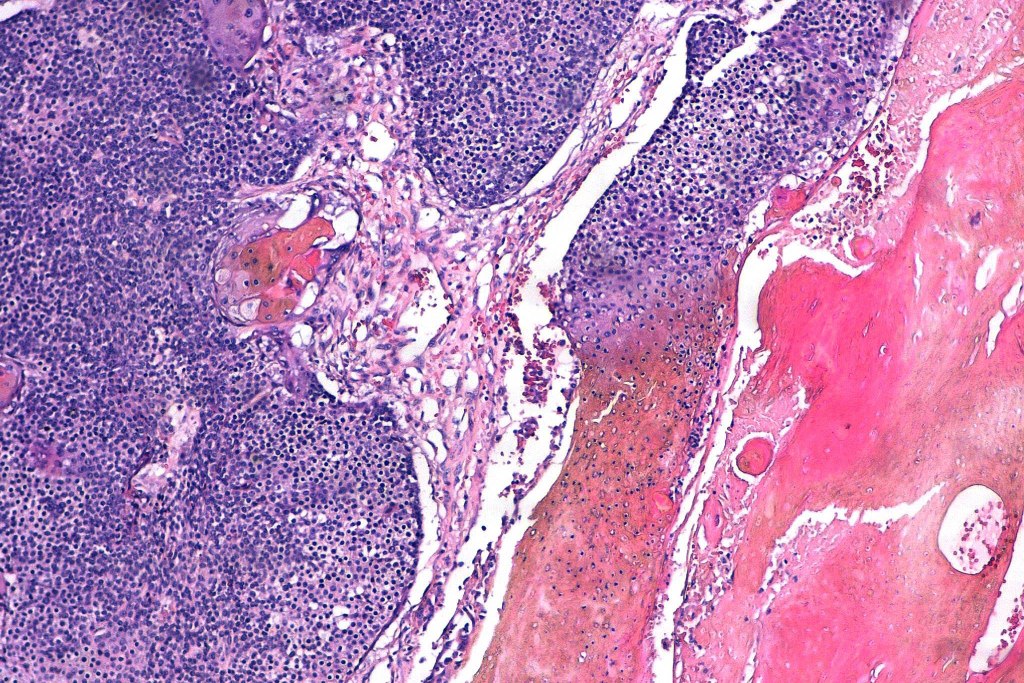

•Multilobulated tumor in dermis +/- subcutaneous fat with a fibrous pseudocapsule

•Basophilic small cells which transition towards supramatricial (orange staining) and ultimately ghost cells with intensely eosinophilic cytoplasm

•Late features include calcification and bone formation

•Foreign body reaction